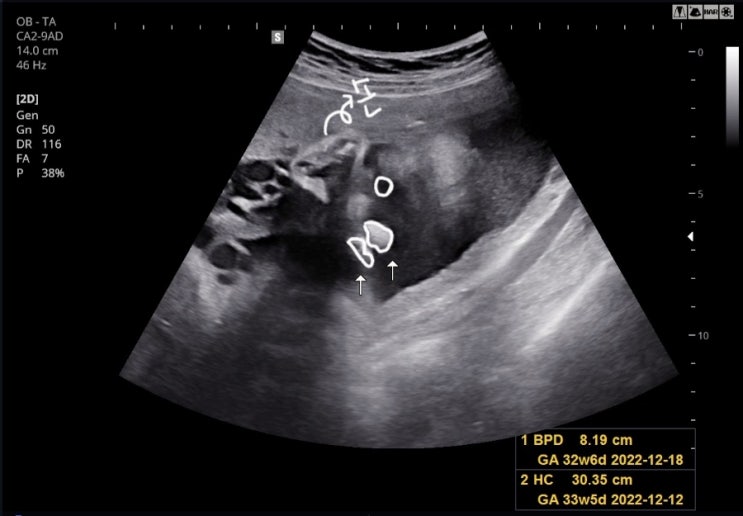

임신 32주~33주차 기록 - 첫 태동검사, 백일해 접종, 허리통증, 유륜습진, 잦은 배뭉침

[임신 32주차 0일 - 22.10.26.] - 어느덧 9개월차를 맞이한 젤리 ? - 산책겸 책 반납하고, 또 대여해서 ...